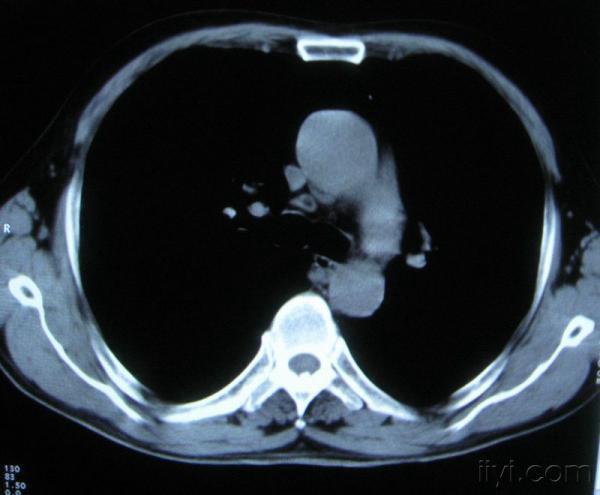

男。60岁,胸片示支气管炎治疗后复查CT。

你指那个肯定是淋巴结,中央系坏死,这很常见,特别在双侧腹股沟会经常看到。这个双侧腋窝及纵隔见多发小淋巴结征。

根据位置考虑应该是淋巴结,密度不均,是因为肿大的淋巴结中心液化坏死